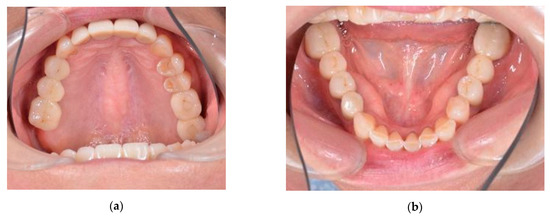

An adult female came to our clinic with complaints about the uncomfortable position of the lower jaw, which had been present for some months. The patient complained of fatigue of the masticatory muscles, increased tension and pain localized in the preauricular areas, and frequent headaches. Upon examination, no intra-articular noise was present when she opened her mouth. Mouth opening was full, straight, and without deviation or deflection. There were two white lines of skin at the corners of her mouth (classic hyperkeratotic dawn lines). Marked teeth wear on the occlusal surfaces of premolars and lower frontal teeth were observed (Figure 1). Metal-ceramic bridges and crowns were present on the elements 16–14, 26, 27, 35–37, 45–47 (Figure 2), and the dental examination showed that the endodontic therapies and implants present were in good condition.

Figure 1. Marked teeth wear on the occlusal surfaces: (a) upper occlusal view; (b) lower occlusal view.